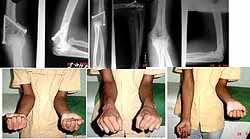

A young 20 years male medical student had been operated for cubitus valgus deformity of his left elbow about a month ago . The pre-operative x-rays were not done and the patient was not having any neurogical disorder with full flexion, extension , supination and pronation movements. The patient was instructed to do active movements of the elbow after 3 weeks.

About 2 days ago the patient experienced severe pain around the eblow with restricted flexion and extension movements but with almost full supination and pronation movements. Somehow the patient was referred to me and after doing several x-rays including the normal right elbow, it appears to me that the patient suffered from "missed Monteggia fracture dislocation" for which unnecessarily wedge osteotomy was done.

Although the patient's parents did not give any history of injury during his childhood. I have put the limb into sling and have asked the patient not to do any kind of exercise for another few weeks till the osteotomized site heals properly. I am attaching the images. Kindly give your valuable suggestions /opinions regarding this case.

The x-rays were a bit fuzzy. Are you sure he did not have a congenital radial head dislocation. They can give you a valgus elbow with pain.